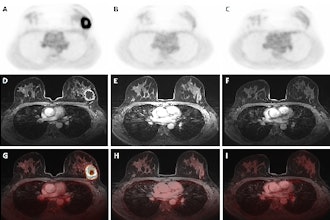

EUSOBI: Positron emission mammography demonstrates worth